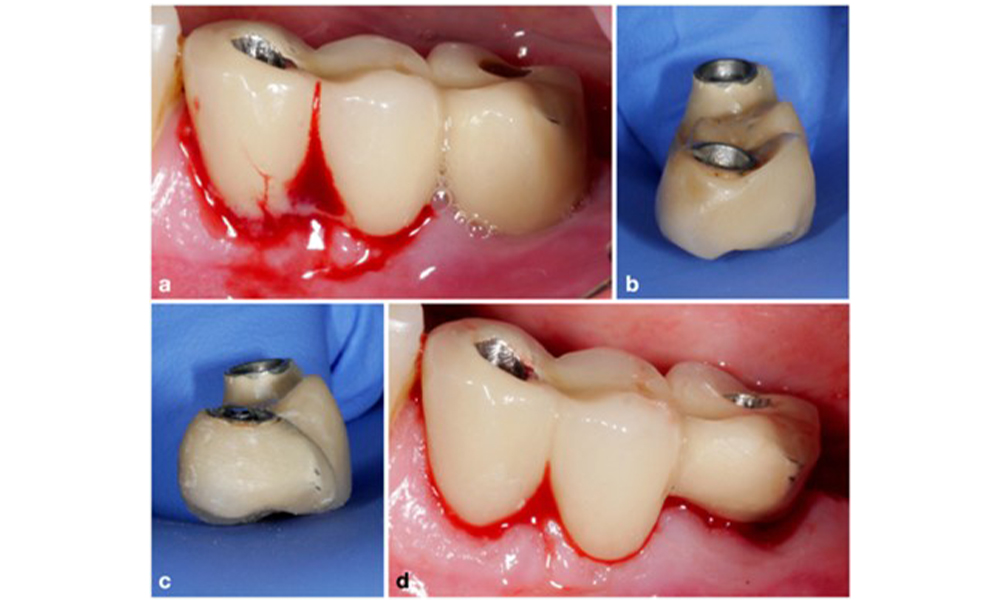

По време на Световния семинар за класификация на пародонталните и периимплантни заболявания и състояния през 2017 г. бяха определени диагностичните критерии за периимплантатен мукозит и периимплантит (Renvert et al. 2018). Периимплантният мукозит се дефинира като (1) наличие на възпаление около импланта (т.е. зачервяване, подуване, линия или капки кръв в рамките на 30 секунди от сондирането), но (2) без допълнителна костна загуба след първоначалното заздравяване (фигура 1 ).